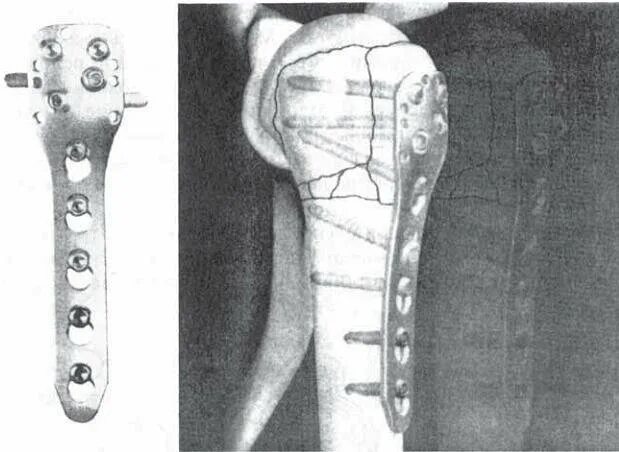

Остеосинтез мрт